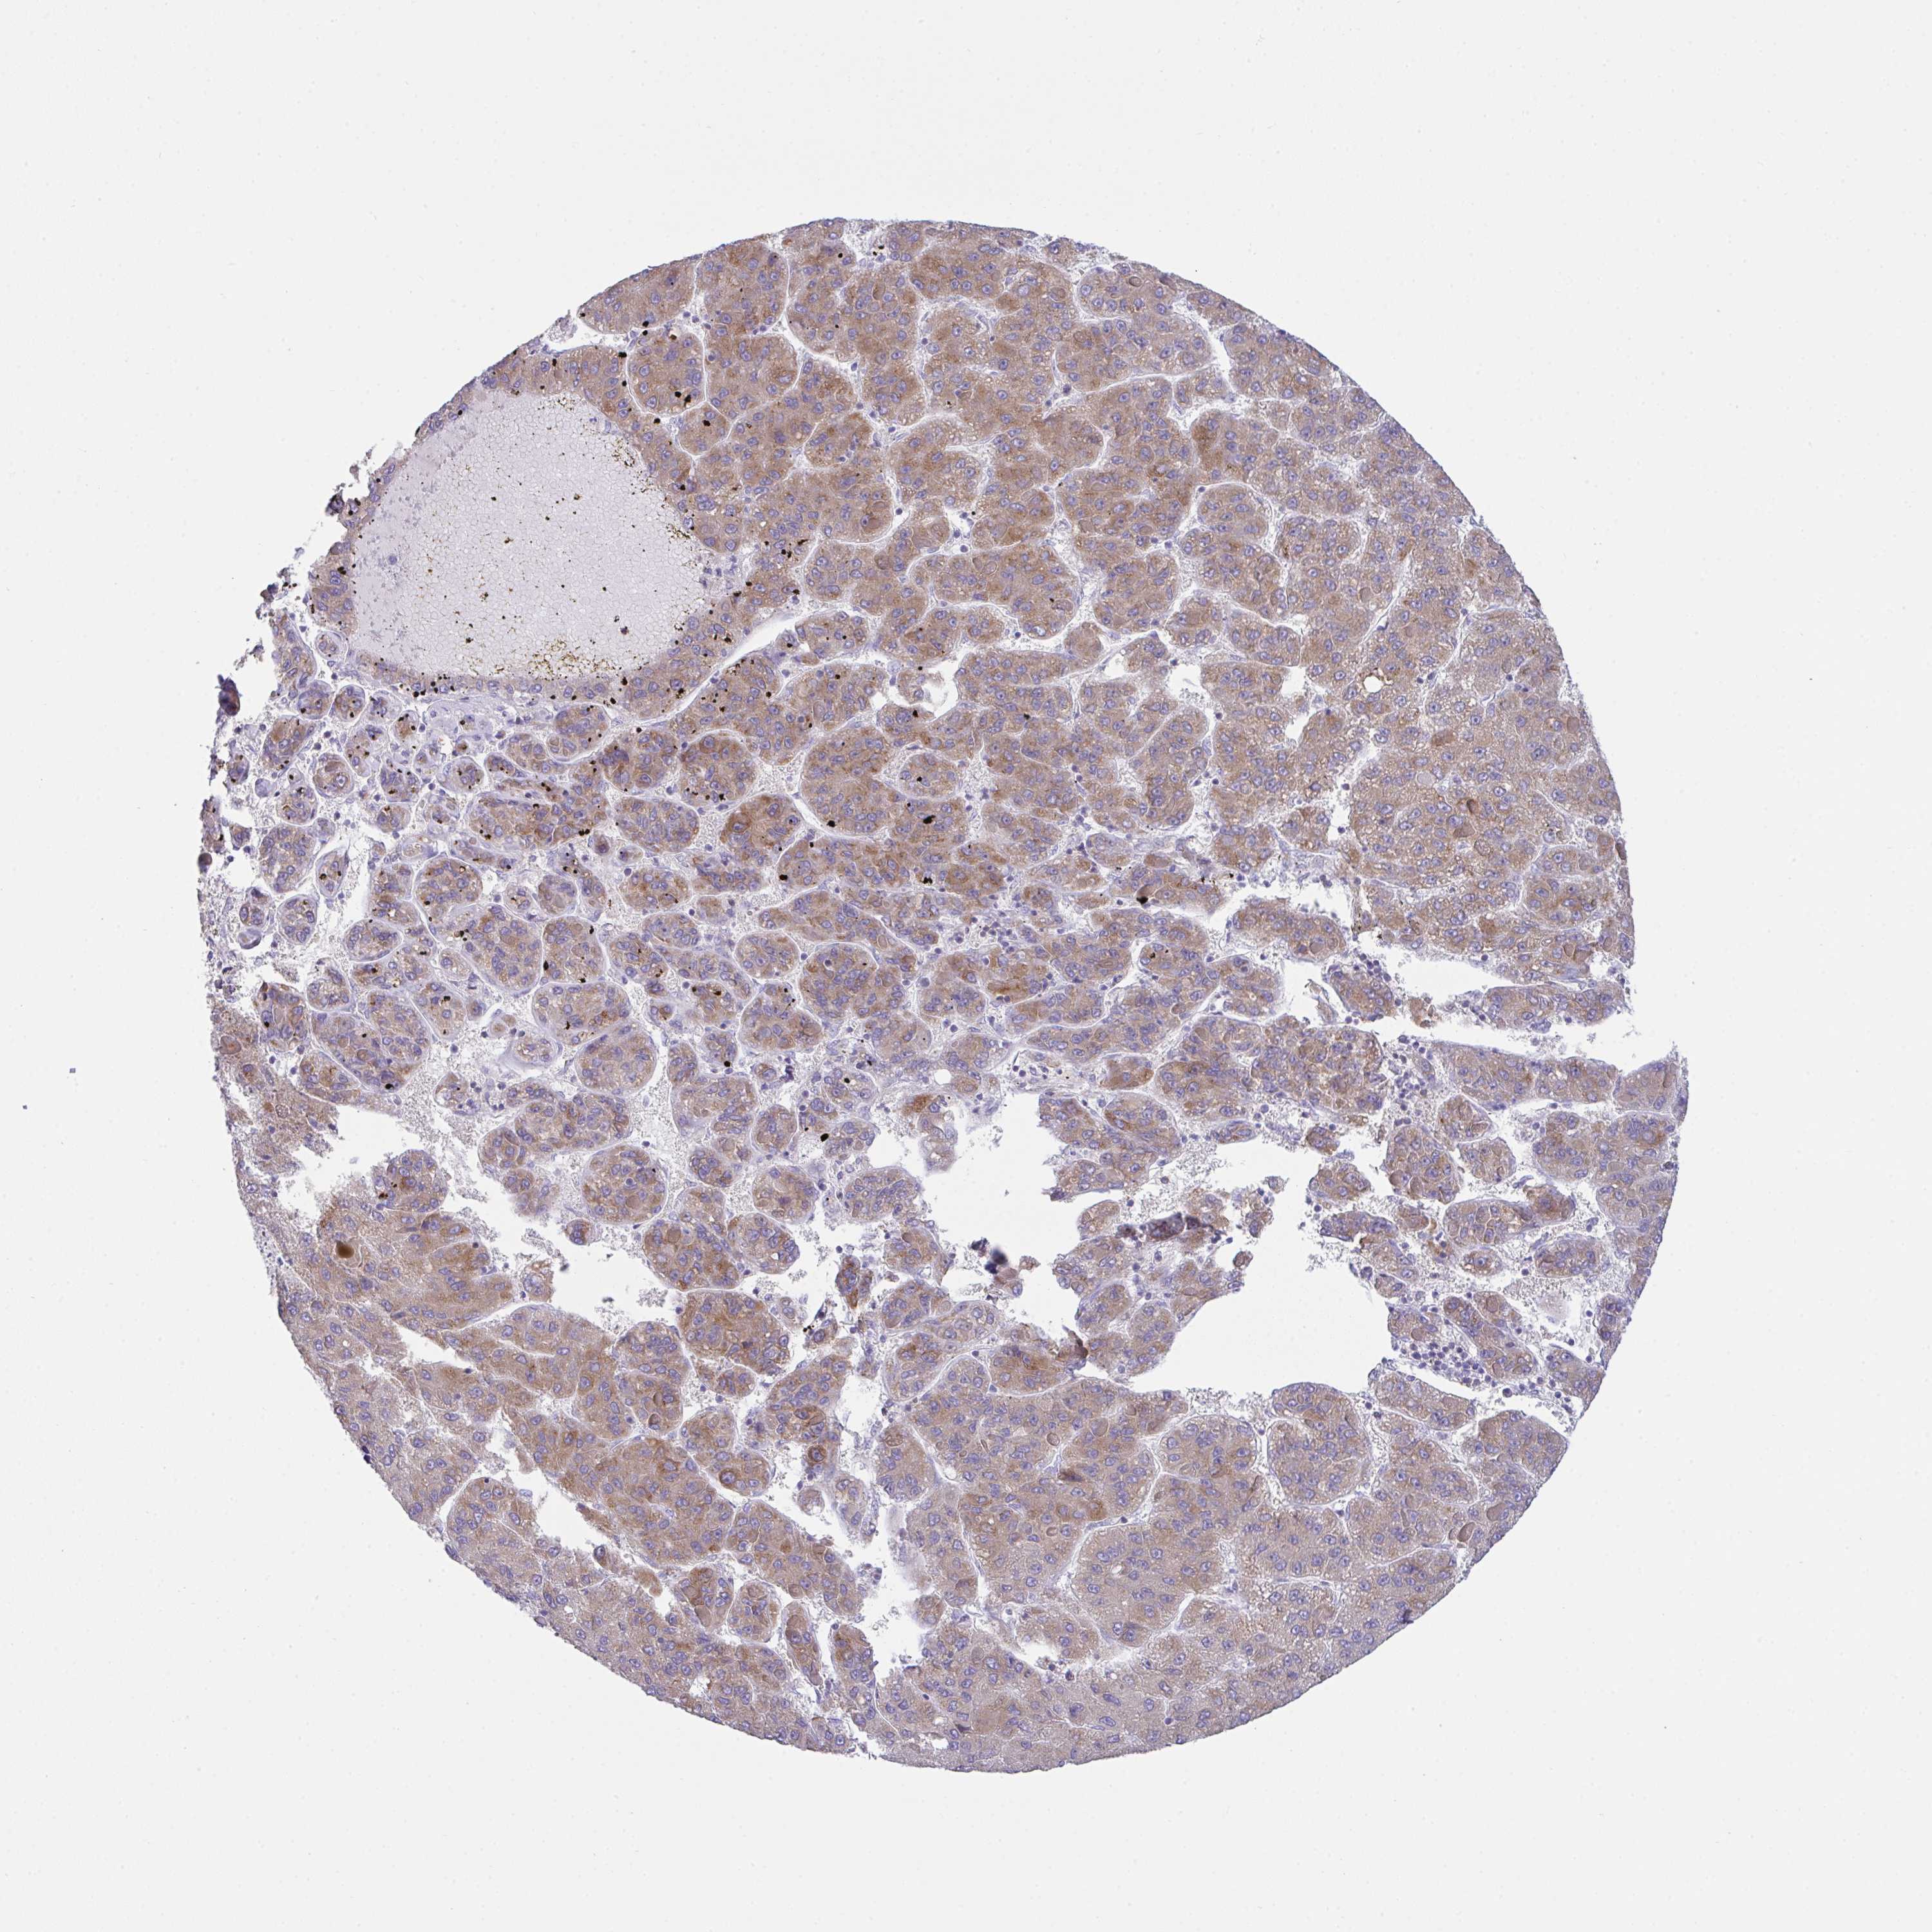

LIVER CANCER - Protein expressioni

A mouse-over function shows sample information and annotation data. Click on an image to view it in a full screen mode. Samples can be filtered based on level of antibody staining by selecting one or several of the following categories: high, medium, low and not detected. The assay and annotation is described here.

Note that samples used for immunohistochemistry by the Human Protein Atlas do not correspond to samples in the TCGA dataset.

Antibody stainingi

Antibody staining in the annotated cell types in the current human tissue is reported as not detected, low, medium, or high, based on conventional immunohistochemistry profiling in selected tissues. This score is based on the combination of the staining intensity and fraction of stained cells.

Each image is clickable and will lead to virtual microscopy that enables deeper exploration of all samples and also displays staining intensity scores, fraction scores and subcellular localization as well as patient and tissue information for each sample.

Antibody HPA055922

Antibody HPA056816

Staining

High

Medium

Low

Not detected

Intensity

Strong

Moderate

Weak

Negative

Quantity

>75%

75%-25%

<25%

None

Location

Nuclear

Cytoplasmic/membranous

Cytoplasmic/membranous,nuclear

Carcinoma, Hepatocellular, NOS

Cholangiocarcinoma